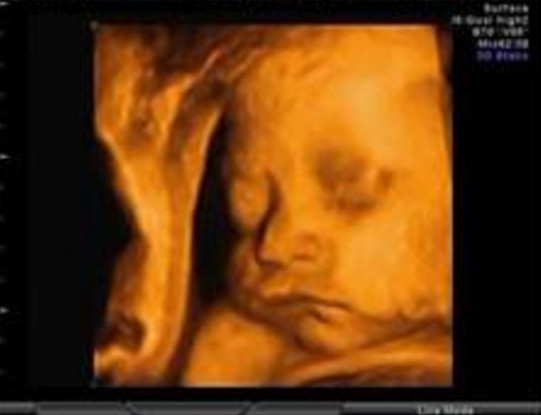

27岁的曹女士,已经怀孕六个月了。三天前,“孕味十足”的她,在丈夫的陪同下来到医院,准备进行提前预约好的四维彩超检查。但是万万没想到,检查结果让她的心情一下跌入低谷!通过影像显示,胎儿嘴唇中间竟然有一指宽的裂痕。经过医生再次仔细确认,腹中的胎儿确实患有唇腭裂,也就是“兔唇儿”。

唇腭裂患儿,是由于牙槽突间骨组织的缺失,造成上颌牙弓的完整性丧失,鼻基底部塌陷,牙槽突裂隙部恒尖牙萌出受阻。胎儿出生以后,需要通过牙槽突植骨术来完成唇部整形。手术具体怎么做,什么时候做,要做几次,这些都要根据孩子的具体病情。至于是否要生出来,这个就要由孕妇及家人自己决定。